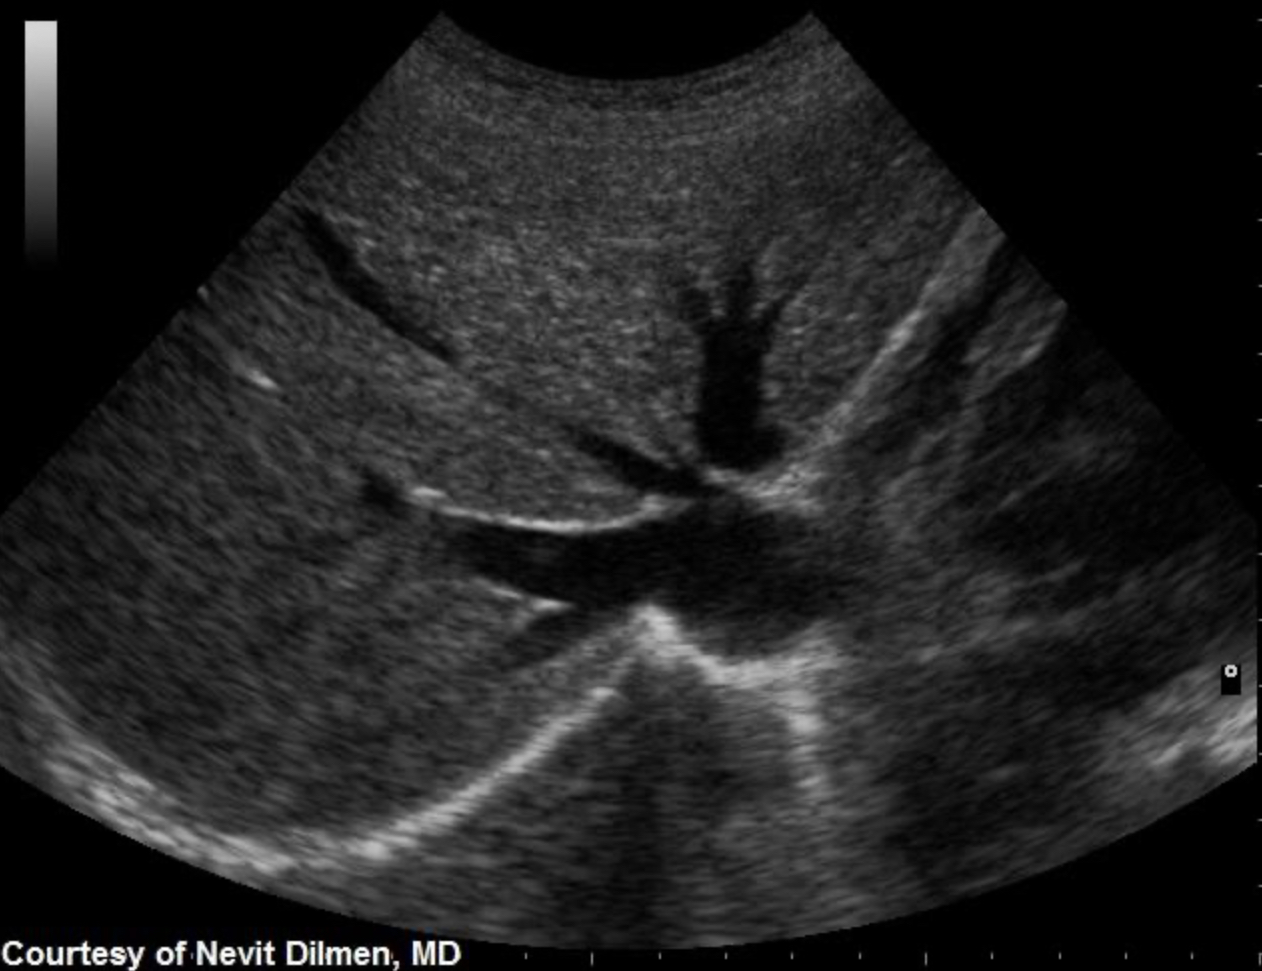

Which of the following statements is true regarding the image displayed?

The gallbladder has a normal variant called a Phrygian cap near the fundal area

Which portions of the gallbladder and/or Billary tree are involved in the formation of a Phrygian cap?

Body and Fundus